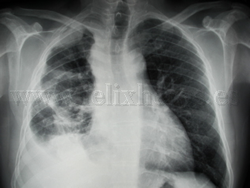

Mesotelioma pleural

Estudios de imagen